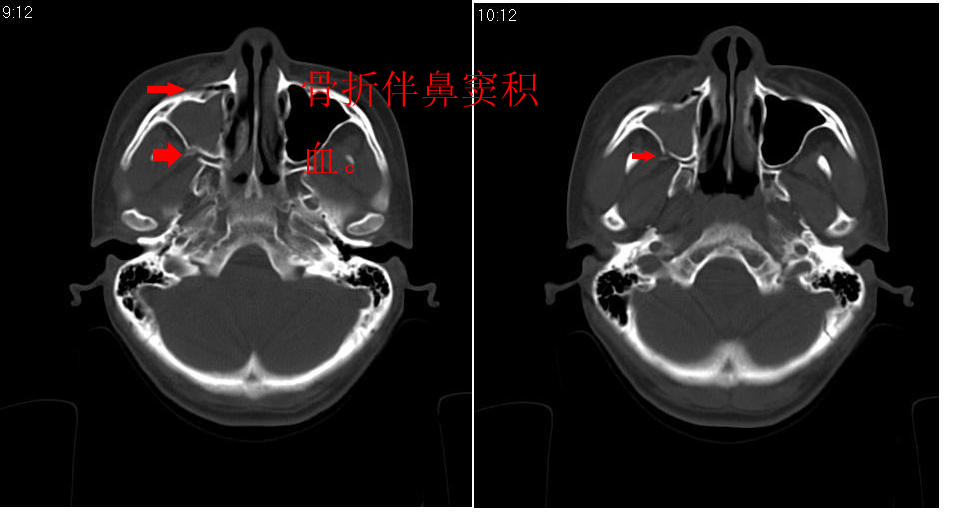

女 18岁,外伤.

右侧上颌窦前壁骨折,窦腔积液.

右侧上颌窦前后壁及右颧骨弓骨折,窦腔积液。

右侧上颌窦前壁、外侧壁骨折,内侧壁可疑骨折,窦腔积液

右侧上颌窦前后壁骨质均不连续,窦腔内见一致性高密度影,右睑部软组织肿胀

1,右上颌窦前后壁骨折,伴窦腔积血可能性大

2,右睑部软组织肿胀

右侧上颌窦前壁、外侧壁、内侧壁骨折,伴窦腔积液;右侧颧弓骨折。

右侧上颌窦粉碎性骨折并窦腔积血。

1 、 右侧上颌窦前壁、外侧壁、内侧壁骨折并窦腔积液(血);右侧上颌窦前壁骨折累及同侧鼻泪管;

2、右侧颧骨骨折。

右侧上颌窦前后壁及颧弓骨质均不连续,窦腔内见一致性高密度影,右面部及眼睑部软组织肿胀

1,右上颌窦前后壁骨折伴窦腔积血,右侧颧弓骨折.

2,右面部及眼睑部软组织肿胀

1.右侧上颌窦前壁、外侧壁骨折,内侧壁骨折,窦腔积血 2.右睑部软组织肿胀

右上颌窦前后壁骨折伴窦腔积气.积血,颧骨弓骨折